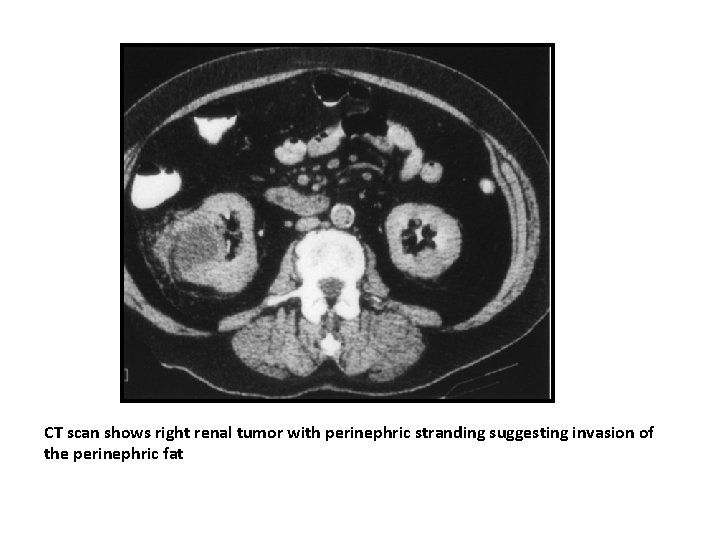

CT scan shows right renal tumor with perinephric stranding suggesting invasion of the perinephric fat